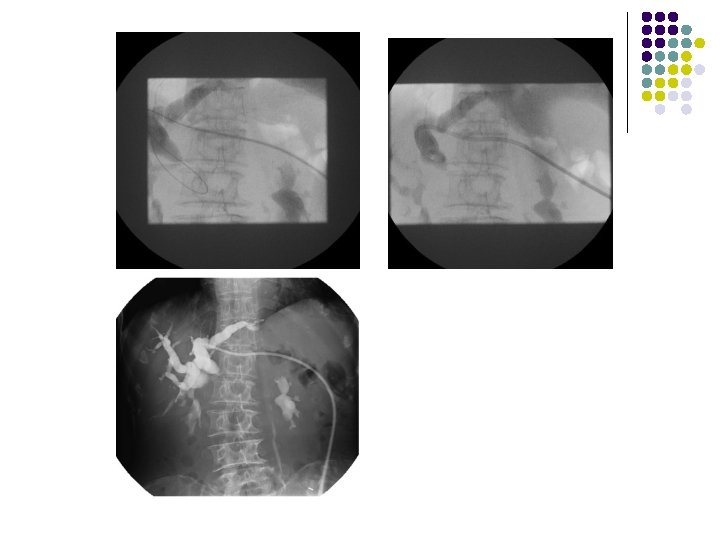

Case l 69歲 女性 Pancreatic ca.